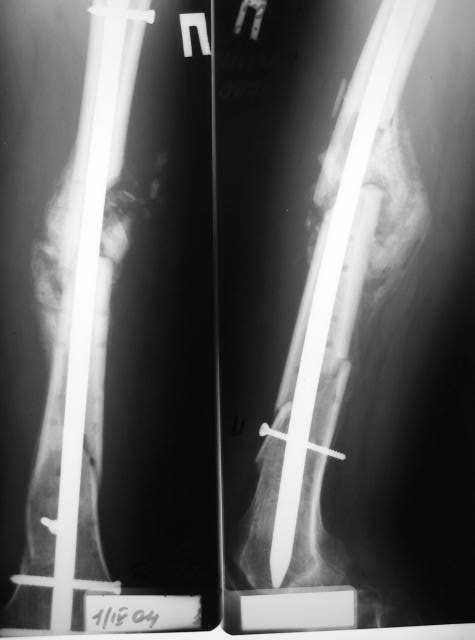

1

2

Наконец, 23 марта сделали и голень.

Сергей Зырянов 10 Апрель 2004, 19:43

Пациент вернулся. Результаты лечения удовлетворяют его.

Буду продолжать наблюдать, лечить.

Раны зажили хорошо, швы снял. Сделали контрольный рентгеновский снимок бедра. Движения в коленном суставе востанавливаются, угол 94 гр.

Больной ходит пока с костылями, с неполной нагрузкой весом тела, он боится больше нагружать.